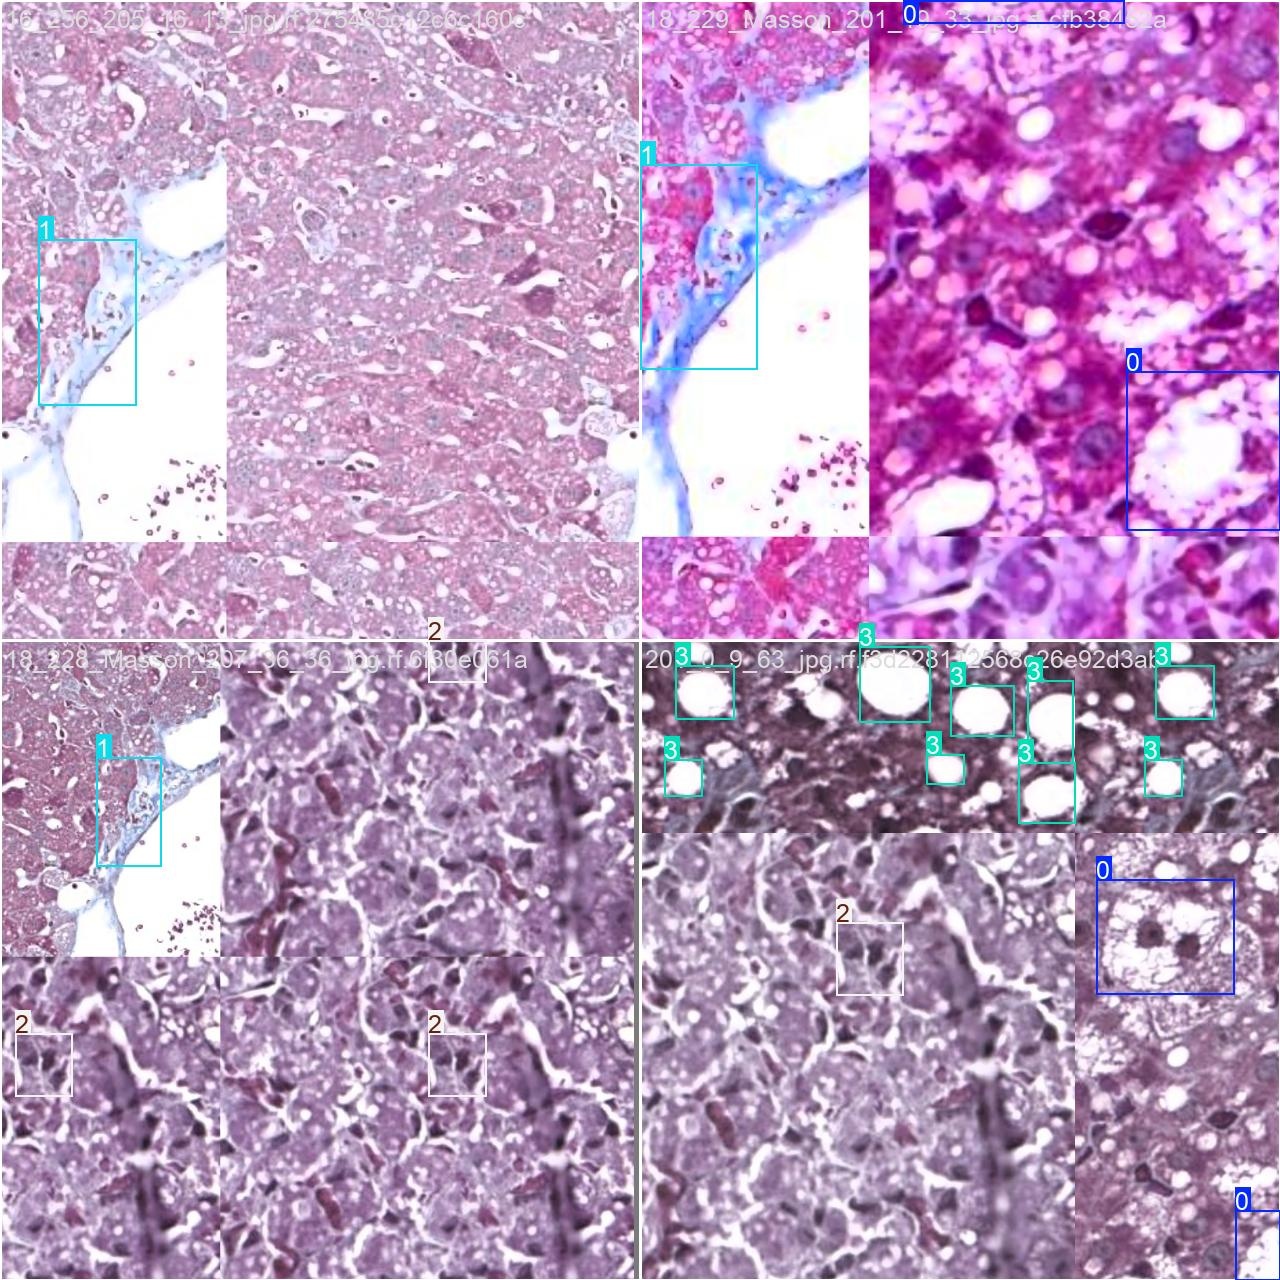

通过涉及多种多样课堂行为相关的图像素材,并利用Labelimg标注工具对获取的所有图像进行标准化标记。这些图像将被划分为三个检测类别:ballooning: 细胞膨胀;fibrosis: 纤维化;inflammation: 炎症;steatosis: 脂肪肝。

2.数据集准备与训练

本研究采用了包含多种肝病相关图像的数据集,并借助Labelimg标注工具完成了对每张图像中目标边界框(Bounding Box)及其分类标签的标注工作。在此基础上,主要基于YOLOv8n模型架构开展了一系列模型训练工作,在完成训练后我们对模型在验证集上的性能进行了全面评估与对比分析。具体而言,在整个实验流程中包含了以下三个关键环节:数据准备阶段、模型训练阶段以及模型评估阶段。实验中所涉及的目标分类类别主要包括细胞膨胀性状、纤维化过程、炎症状态以及脂肪肝类型等四个核心指标。根据实验数据显示,在所使用的数据集中总计包含3976张图像样本信息,在具体分布上表现为:用于训练的样本数量为2782张,在验证阶段使用了794张样本,在测试过程中则采用了400张新的样本作为代表进行分析比较

部分标注如下图所示: